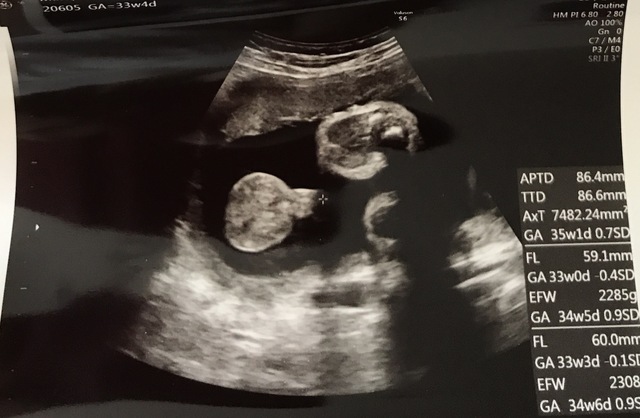

33週5日(33w5d・男の子)|みーひろ916 さん(30歳)

エコー写真撮影時のエピソード:

男の子と完全にわかる写真。 分かってはいましたが、もう一度先生に聞きました。 お顔が見えなかったのが残念です。

赤ちゃんが大きすぎるみたいで、なるべく早く産めるように頑張らないとしんどいと言われたので、里帰りしたらいっぱい体を動かして早く降りてくるように頑張ります。